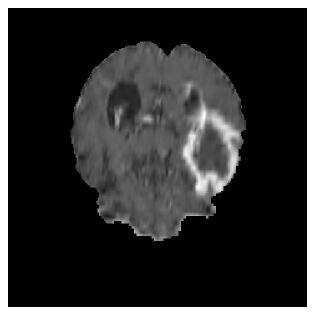

Appendix A Qualitative results

Figures 4 and 5 present the segmentation results for a patient from the BRATS dataset, visualized on a randomly selected slice. Figure 4 illustrates how tumor segmentation evolves over multiple episodes in S1 across different approaches including cumulative, naive, our approach, and the best buffer-free strategy (SI, =2). The cumulative approach, which trains on all encountered datasets together, maintains segmentation consistency across episodes but introduces significant amounts of false positives, particularly in the upper left area of the brain images. These misclassifications highlight its inability to generalize well across datasets despite access to all previous data. The naive approach, which learns sequentially without any continual learning strategy, suffers from severe catastrophic forgetting. While it initially segments well, performance deteriorates over episodes, leading to a near-complete loss of segmentation capability by the final episode. The SI (=2) approach, a regularization-based buffer-free CL strategy, performs reasonably well in early episodes but shows a significant performance decline over time. By the last episode, much of the tumor was no longer segmented, indicating difficulty in retaining prior knowledge. In contrast, our proposed approach initially produces more false positives but progressively refines its segmentation. By the final episode, it accurately retains the tumor region while minimizing misclassifications, demonstrating strong knowledge retention and adaptability across episodes. This suggests that our approach effectively mitigates catastrophic forgetting while maintaining segmentation performance over sequential learning.